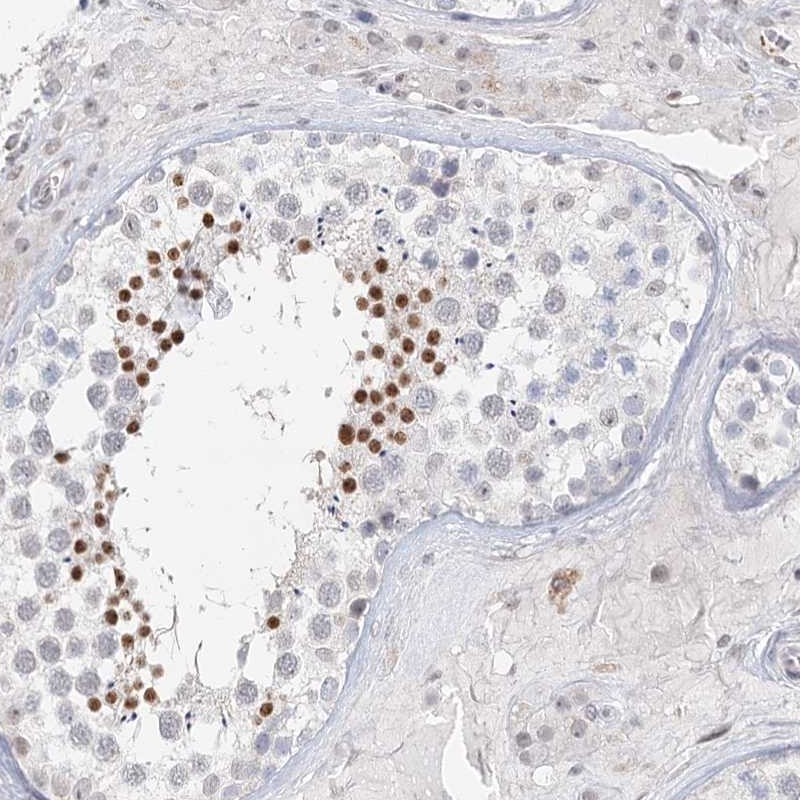

Immunohistochemical staining of human testis shows strong nuclear positivity in spermatids.